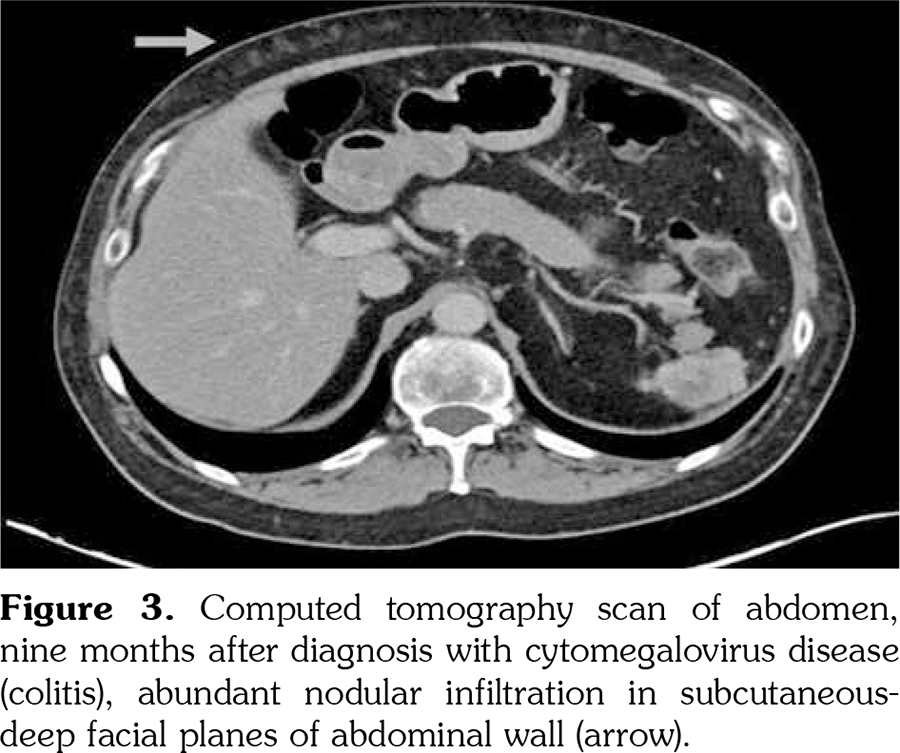

Eight months afterwards, he was hospitalized with a body temperature of 38.3°C and fatigue. On this admission, laboratory examinations revealed high C-reactive protein (4.76 mg/dL) level while no bacterial growth was observed in blood cultures. PCR test detected CMV DNA at 2,400 copies/mL. CT scan of the abdomen showed new abundant nodular infiltration in the subcutaneous-deep facial planes of the abdominal wall (Figure 3). Abdominal subcutaneous fat tissue true-cut biopsy was performed and CMV DNA was detected in the quantitative PCR assay of tissue specimen. He was put on oral valganciclovir treatment while mycophenolate mofetil was permanently discontinued. Following antiviral therapy, azathioprine was started and peripheral blood PCR assay revealed CMV DNA of 57 copies/mL at one month of this treatment.